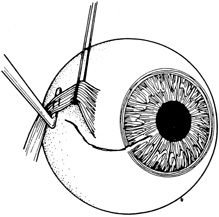

There are many options in selecting suture material for scleral closure. Although some surgeons prefer nonabsorbable sutures (i.e., 8-0 nylon or silk), others may use absorbable materials (i.e., 7-0 polyglactin 910). For larger defects, nonabsorbable sutures should be used. When suturing gaping wounds, it may be helpful to advance the needle completely through one wound margin and then reload the needle holder before making a second pass, thus avoiding globe distortion (Fig. 17). For closing sclera over prolapsed uvea, the wound is often most easily closed from the anterior (limbal) end with interrupted sutures, which are placed successively, proceeding posteriorly. This is called the “zippering” or “close-as-you-go” technique. With this technique, sutures are placed in close proximity to one another in an attempt to achieve oversewing of the uveal tissue with the sclera. The surgical assistant may use a spatula to gently depress the uvea into the eye during suture tightening to avoid tissue incarceration during scleral closure (Fig. 18). Another suturing strategy is to successively bisect the wound while having the assistant use a spatula to press any prolapsed tissue back into the eye as sutures are tightened.